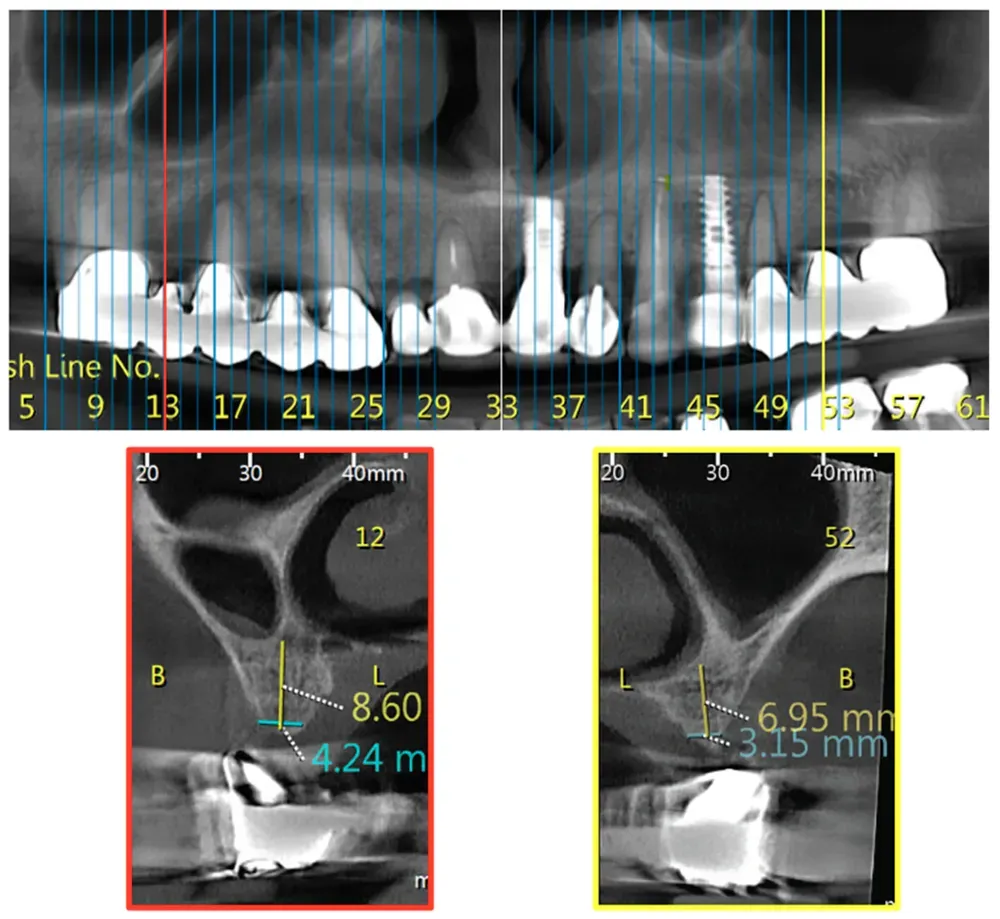

Yahya e collaboratori hanno sviluppato un sistema di classificazione che divide questa variante in classi orizzontali mesio-distali e divisioni verticali. Ma ciò che sorprende di più in questo interessante articolo è la frequenza relativamente alta della variante riscontrata dagli autori. (https://doi.org/10.3390/jcm10194293)

Nella Classe 1, il confine tra la cavità nasale e l’antro mascellare si trova sopra la parte distale del canino. In base ai dati raccolti in questo studio, si trova nel 17.2% dei casi.

La Classe 2, dove il confine naso-sinusale si trova tra il margine distale del canino e quello del secondo premolare, appare nel 66% dei casi esaminati. La Classe 3, con il confine distale al margine mesiale del primo molare, si manifesta nel 16,8% dei pazienti.

Queste caratteristiche anatomiche possono essere diverse tra un lato e l’altro. È possibile riscontrare una classe su un lato e una morfologia diversa sull’altro. Vedi le immagini che seguono.

Classe 2 della variante big nose del seno mascellare

Classe 2

Classe 3 bilaterale della variante Big nose del seno mascellare

Classe 3 bilaterale